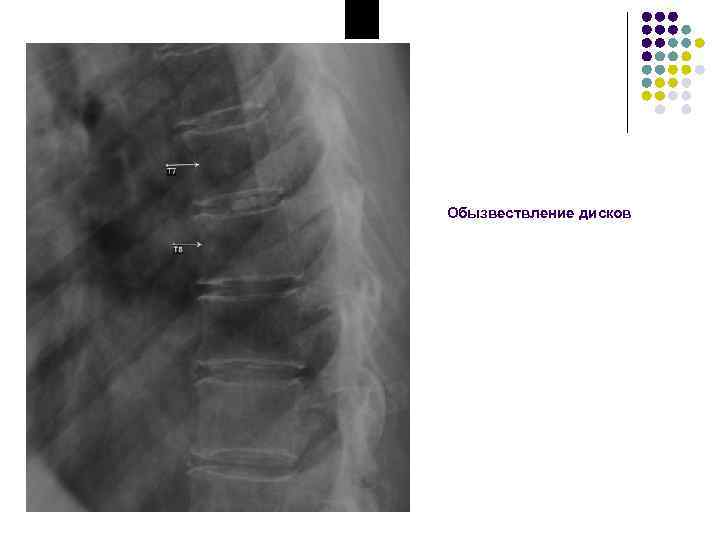

Обызвествления межпозвоночного диска • Чаще локальное обызвествление желатинозного ядра или отдельных участков фиброзного кольца • Редко обызвествляется весь диск • Часто сочетается с умеренным остеохондрозом передних участков диска • Как правило, не вызывает никаких субъективных и объективных симптомов, являясь случайной находкой

Обызвествление дисков

Обызвествление межпозвоночного диска